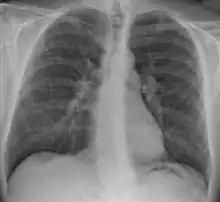

Chest X-ray showing the typical nodularity of sarcoidosis, predominantly in the hila of the lungs. | |

Chest radiograph changes are divided into four stages:[105]

- bihilar lymphadenopathy

- bihilar lymphadenopathy and reticulonodular infiltrates

- bilateral pulmonary infiltrates

- fibrocystic sarcoidosis typically with upward hilar retraction, cystic and bullous changes

Although people with stage 1 radiographs tend to have the acute or subacute, reversible form of the disease, those with stages 2 and 3 often have the chronic, progressive disease; these patterns do not represent consecutive "stages" of sarcoidosis. Thus, except for epidemiologic purposes, this categorization is mostly of historic interest.[28]